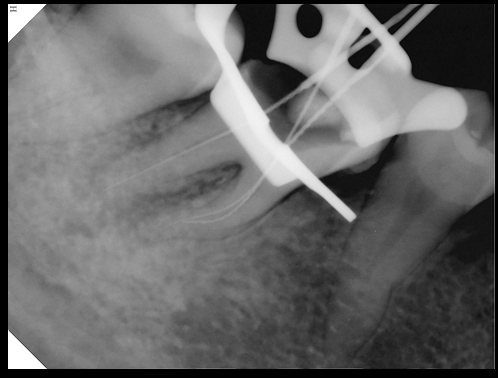

CR/DR 牙齿分割阶段记录

当前进展

- 完成了 CR/DR 牙齿相关分割训练

- 当前结果已经达到阶段预期,但仍有细节问题需要继续处理

相关测试

遇到的问题

- 训练过程中出现过 mask 下移问题

- 部分结果会出现 box 填充异常

- mask 边缘仍然有比较明显的锯齿感

参考

第二版算法问题测试

Updated: 2026-04-13(更新日期)

| 第一版 | 第二版 | 是否解决 | |

|---|---|---|---|

![]() | ![]() ![]() 边角识别有问题 龋齿识别不全 牙髓识别不全 | ![]() | 解决 |

![]() | ![]() 边角识别有问题 识别信息有误 自查(牙冠识别不全) | ![]() | 解决 |

![]() | ![]() ![]() 边角识别有误 大范围填充识别遗漏 | ![]() | 解决 |

![]() | ![]() 识别信息不全 | ![]() | 解决 |

![]() | ![]() ![]() 边角问题 牙胶识别不全 牙冠识别不全 | ![]() | 解决 |

![]() 换图片 | ![]() | ![]() 牙冠部分稍微白了一些就识别成小范围修补,部分判断异常 | 部分解决,修复类略敏感,牙冠部分稍微白了一些就识别成小范围修补,部分判断异常。 |

![]() | ![]() ![]() 牙冠识别不全 牙髓不全 根尖炎龋齿识别有误 | ![]() | 解决 |

![]() | ![]() | ![]() | 解决 |

![]() 换图片 | ![]() | ![]() | 解决 |

![]() | ![]() 牙冠识别有误 | ![]() | 解决 |

![]() 换图片 | ![]() ![]() 边角识别有误 | ![]() 修复类敏感 | 部分解决,图像过白,导致修复类判断异常。 |

![]() 换图片 | ![]() 牙冠识别不全 | ![]() 修复类敏感 | 部分解决,图像过白,导致修复类判断异常 |

结论:修复类出现了不鲁棒的情况,后续需要加入轮廓的扩充数据进行增强。